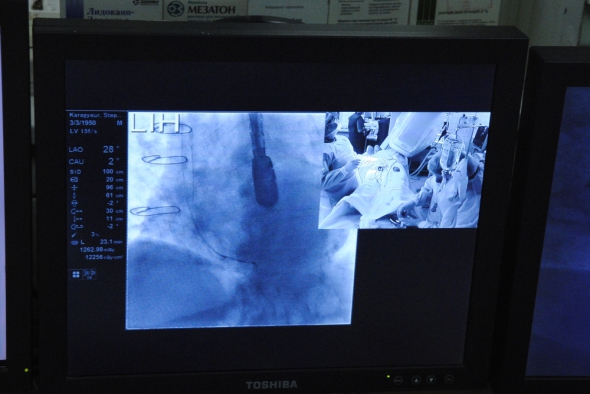

7 грудня у Києві фахівці Національного інституту серцево-судинної хірургії ім. Н.М. Амосова вперше в Україні провели операцію протезування клапана аорти без розрізу грудної клітки пацієнта.

Інститут став першим лікувальним закладом в країні, в якому проводять транскатетерне протезування аортального клапана, використовуючи систему CoreValve компанії Medtronic, як альтернативу операції на відкритому серці для пацієнтів, які потребують заміни клапана.

Першим став 83-річний пацієнт. У невеликий розріз на нозі штучний клапан серця йому ввели за допомогою катетера через артерію.

Принцип нового методу полягає в тому, що за допомогою внутрішньосудинного катетера протез клапана вводять в серці, де знаходиться зношений аортальний клапан. Після отримання європейського сертифікату CE в березні 2007 року систему CoreValve імплантували більш ніж 35000 пацієнтам у всьому світі. Успішність операції - 98 відсотків серед важких пацієнтів з вираженим стенозом аорти.